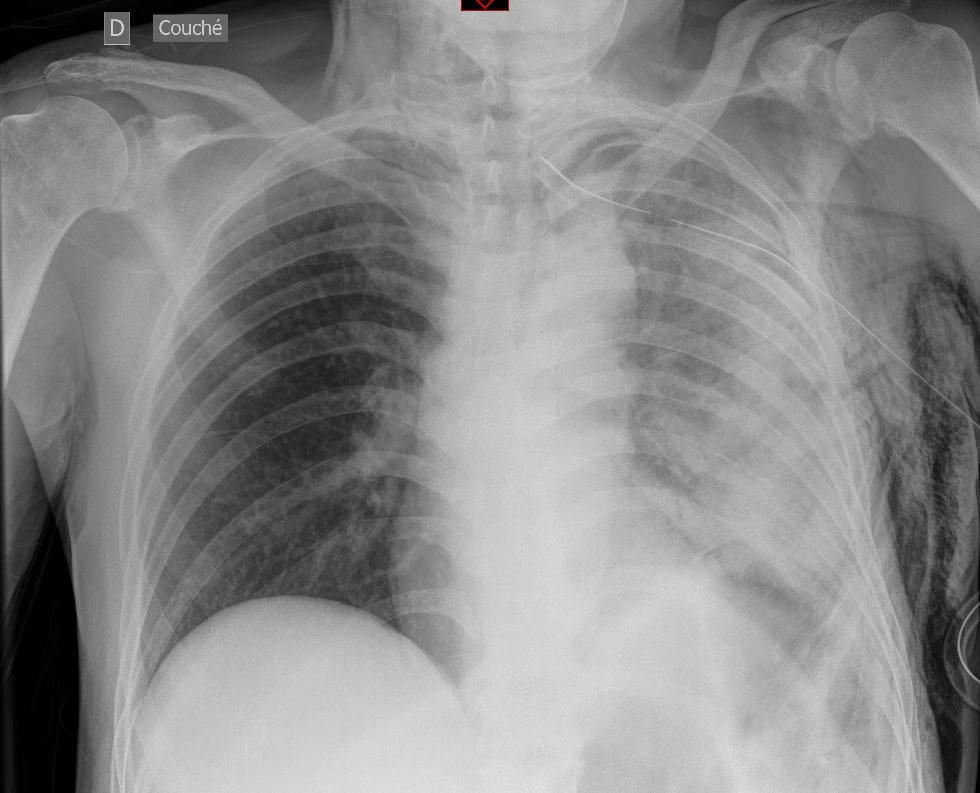

Peu de temps après avoir mis en place un drain thoracique à un jeune patient de 32 ans souffrant d’un premier épisode de pneumothorax spontané primaire, tu constates qu’il développe une tachypnée avec une désaturation à 85% à l’air ambiant et une douleur respiro-dépendante.

Après avoir mis en place un masque à oxygène à haute concentration, le patient reste tachypnéique à 25/​min avec une saturation à 91%.

Tu effectues une radiographie du thorax :